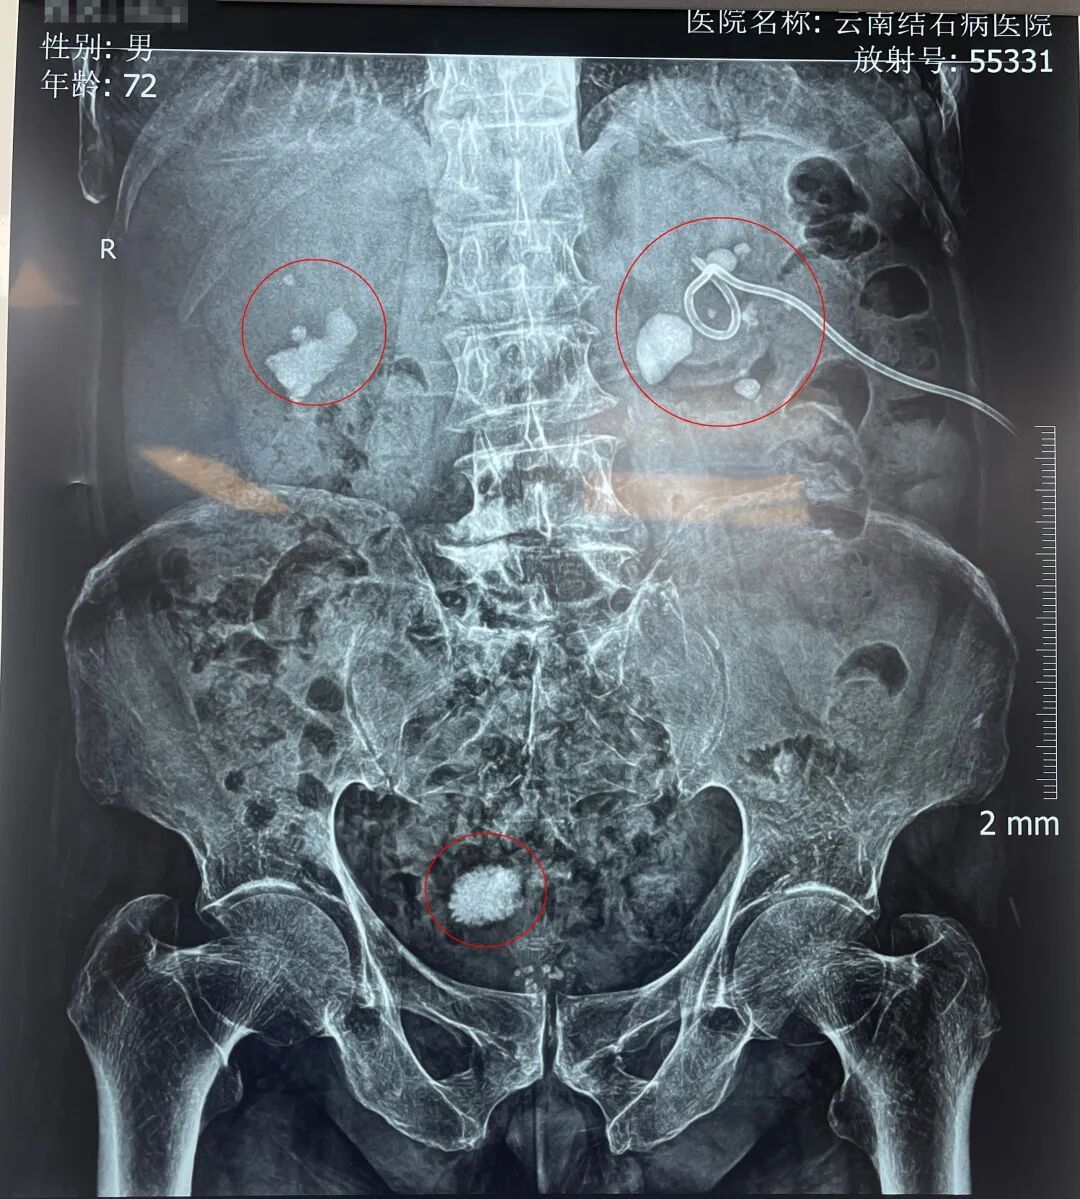

周爷爷的检查片子

入院后,黄鸿宾主任为周爷爷安排了全面系统的检查。结果显示,其身体状况犹如一座年久失修的老屋,多处功能受损:前列腺增生伴钙化、膀胱结石、双肾多发性结石伴积水、脂肪肝、高血压等。